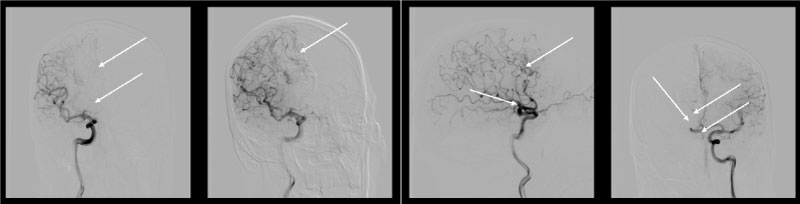

The second stage was the microcatheter Sonic® (BALT) 1.5 F is wound up in the cavity of the aneurysm, positioned in the area of the dome. Inflated balloon on a guide catheter Corail +® (BALT) 6F during embolization. Blood pressure is reduced to 80/60 mmHg, embolization is performed. After embolization the balloon on the guide catheter was deflated. On control angiography, we have found a good result: subtotally embolized AVM and completely "turned off" aneurysm while preserving the anterior connecting artery (ACoA) (Figure 5).

Figure 5: Control cerebral angiography showing embolized AVM, and flow-related aneurysm. View Figure 5